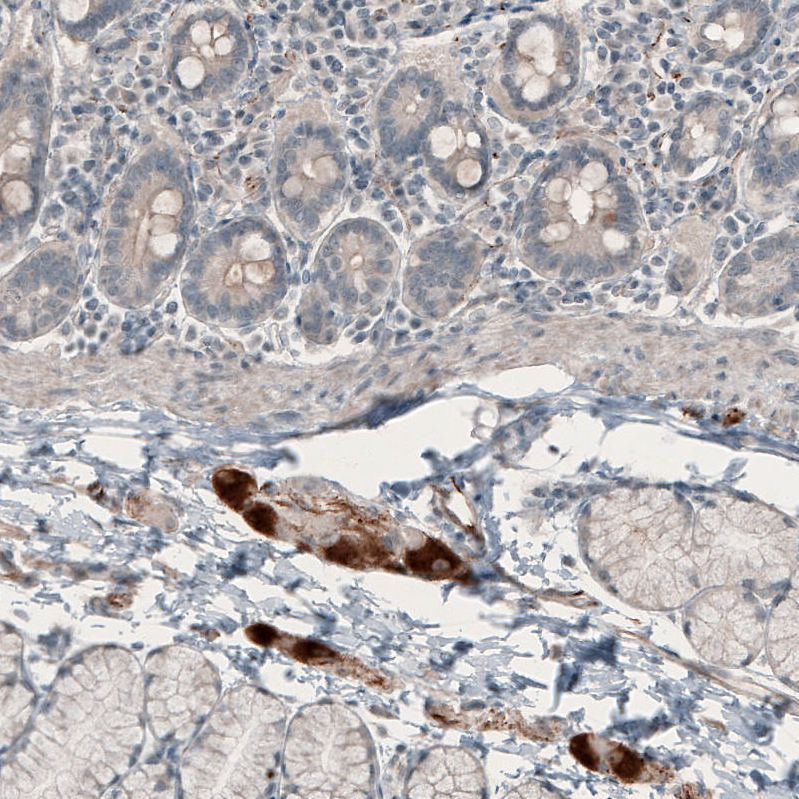

Immunohistochemical staining of human duodenum shows strong cytoplasmic positivity in a subset of cells in the peripheral ganglion.